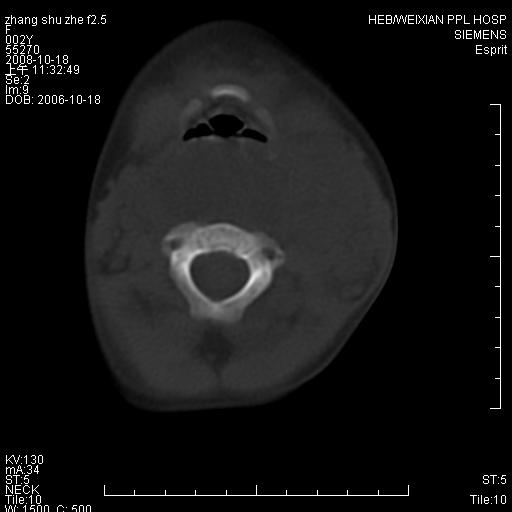

以下是引用dyqct在2009-2-10 21:04:00的发言:[br]年龄?性别?有发烧吗?[br]鼻咽部、口咽部、喉咽部及颈椎前间隙广泛肿厚,明显占位效应并致相应组织变形。ct值22-28hu。[br]考虑:1、颈前脓肿可能性大;[br] 2、建议增强或治疗后复查。

以下是引用jiangjing在2009-2-11 11:37:00的发言:[br]急性病程,鼻咽部、口咽部、喉咽部及颈椎前间隙广泛肿厚,明显占位效应并致相应组织变形.考虑颈部感染性病变(脓肿?);建议行进一步检查。